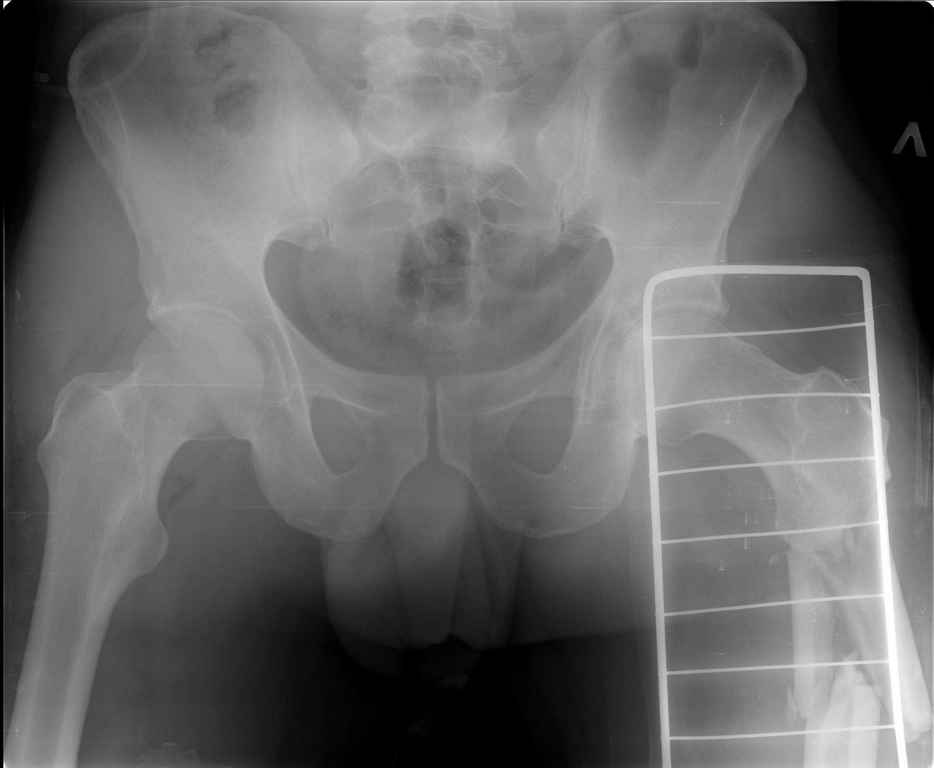

Ds: ТСТ. ЗЧМТ. СГМ. ЗТГК. О/фрагментарный перелом левого бедра. З/оскольчатый перелом с\3 левого плеча. Перелом левого локтевого отростка. З/перелом наружного мыщелка б/берцовой кости в/3 м/берцовой кости левой голени. при поступлении, ПХО раны левого бедра( рана 1х1см по наружной поверхности бедра в с/3) налажено скелетное вытяжение , и гипсовая лонгета на левую в/конечность. Находился в реанимации. 17.02.11 был прооперирован: БИОС левого плеча, о/синтез левого локтевого отростка по Веберу, БИОС левого бедра (длинная версия Fi-Can Sanatmetal диаметр 10мм), мыщелок голени трогать не стали.при остеосинтезе бедра возникли трудности при закрытй репозиции перелома в н/3, в связи с чем решили открыться внизу , отрепонировали без особого труда и выполнили блокирование во фронтальной плоскости 3-мя винтами + 1 винт спереди гвоздя (промазал). Убрал костодержатель, все нормально, контроль ЭОПом стояние отломков нормальное, зашились. На контрольной R-мме на утро выявлено вторичное смещение дистального отломка. Левая нога по сравнению со здоровой удлиннена до 2,5см( это за счет вальгусной установки гвоздя в проксимальном отделе, боялся свалиться на варус). Теперь думаем как поправить положение отломков в н/3, и зафиксировать так чтобы не съехало. Наше предложение расшиться в н/3 бедра, разблокироваться, перелом отрепонировать вновь и установить 1или 2отклоняющих винта в сагитальной плоскости, затем заблокироваться во фронтальной плоскости снова. Помогите советом, как выйти достойно из сложившейся ситуации. Заранее спасибо.

С моей точки зрения удлинение (если таковое имеется) произошло не за счёт вальгусной установки стержня. На контрольной рентгенограмме блокирующие винты точно расположены в шейке бедренной кости и в центре ротации головки. И даже если выбран стержень с максимальным из выпускаемых углом в 135 градусов, он не обеспечит столь значительного удлинения конечности. Увеличенный шеечно-диафизарный угол на контрольной рентгенограмме со стержнем объясняется наружной ротацией конечности при рентгенографии и возникающем при этом проекционном искажении ШДУ. Скорее всего, удлинение конечности объясняется наличием диастаза между отломками в вертельной области.

Важно установить из-за чего произошла вальгусная деформация дистального отломка (при условии, что на операционном столе после дистального блокирования её не было). Если взять в руки стержень и ввести в дистальное круглое отверстие блокирующий винт, то из-за разности в диаметрах блокирующего винта и диаметра блокирующего отверстия в стержне, возможно отклонение стержня во фронтальной плоскости до 13 градусов в каждую из сторон. Если второе отверстие для блокирования на дистальном конце стержня круглое, проблема «качания» дистального отломка во фронтальной плоскости на одном блокирующем винте при инфраистмальных переломах решается введением второго блокирующего винта во фронтальной плоскости. Если второе блокирующее отверстие овальное, введение второго блокирующего винта во фронтальной плоскости эту проблему не решит (кажется, это ваш случай). В таком случае лучшим решением является введение блокирующего винта в сагитальной плоскости через соответствующее отверстие стержня (это всегда лучший вариант). Однако в выбранном стержне такого отверстия нет. Поэтому мы бы поступили следующим образом. Удалили бы все дистальные блокирующие винты. Выполнили бы открытую репозицию дистального перелома на стержне с ликвидацией вальгусной деформации. Мне представляется, что это технически выполнимо, поскольку стержень не погружен в мыщелки глубоко и уже произошло вторичное смещение. Перелом предварительно фиксировали бы костодержателем. В качестве противоупора в заглушку стержня необходимо вставить отвёртку. Ударами по костодержателю в проксимальном направлении постарались бы ликвидировать диастаз в вертельной области. Выполнили бы дистальное блокирование двумя винтами во фронтальной плоскости, причём винт в овальном отверстии провели бы по его проксимальному краю. На проксимальном конце дистального отломка максимально близко к месту перелома в сагитальной плоскости провели бы два винта poler по обеим сторонам стержня.